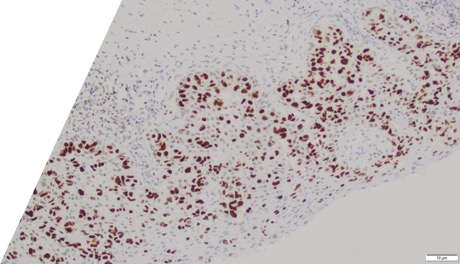

Large round malignant cells with pale cytoplasm and enlarged nucleolus and prominent nucleoli are present within the epidermis. The cytoplasm contains mucin. Differential diagnosis include HSIL, Paget disease (primary or secondary), and melanoma in situ. The lesional cells are strongly positive for CK7, CK20, CAM5.2 and GATA3, scattered positive for p63; and patchy staining for p16, negative for ER and SOX10. High-risk HPV-ISH is negative.

Patient's history of invasive high-grade urothelial carcinoma is shown. The tumor cells showed similar morphological features to the tumor cells in current specimen. The findings are compatible with secondary involvement by previously diagnosed urothelial carcinoma.

Due to morphological similarity both architecturally and cytologically, precise diagnosis based on H&E alone can be challenging, and IHC can be overlap. The current case highlight the importance of clinical history in establishing an accurate diagnosis for patients with an extension of urothelial carcinoma into the GYN tract.